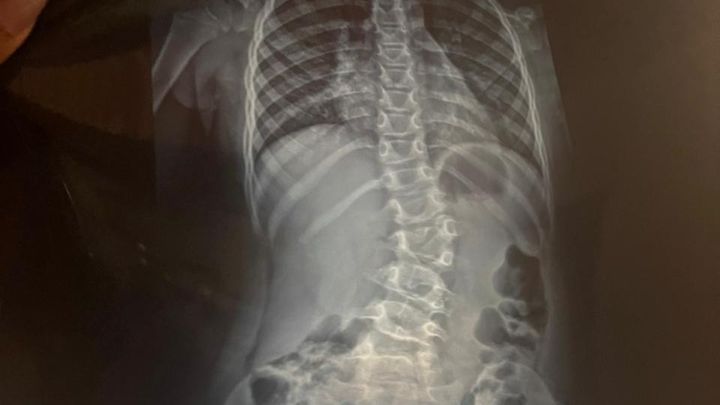

At just three months in the womb, during a routine ultrasound, Emily was diagnosed with thoracic lumbar scoliosis. We were told it wouldn't correct itself, that instead it would worsen, and that surgery would be necessary when she turned ten.

However, our little girl has grown so much in the past few years, and her scoliosis has progressed faster. At only 7, she's already experiencing major pain. Surgery is no longer something we can postpone. It's needed now.